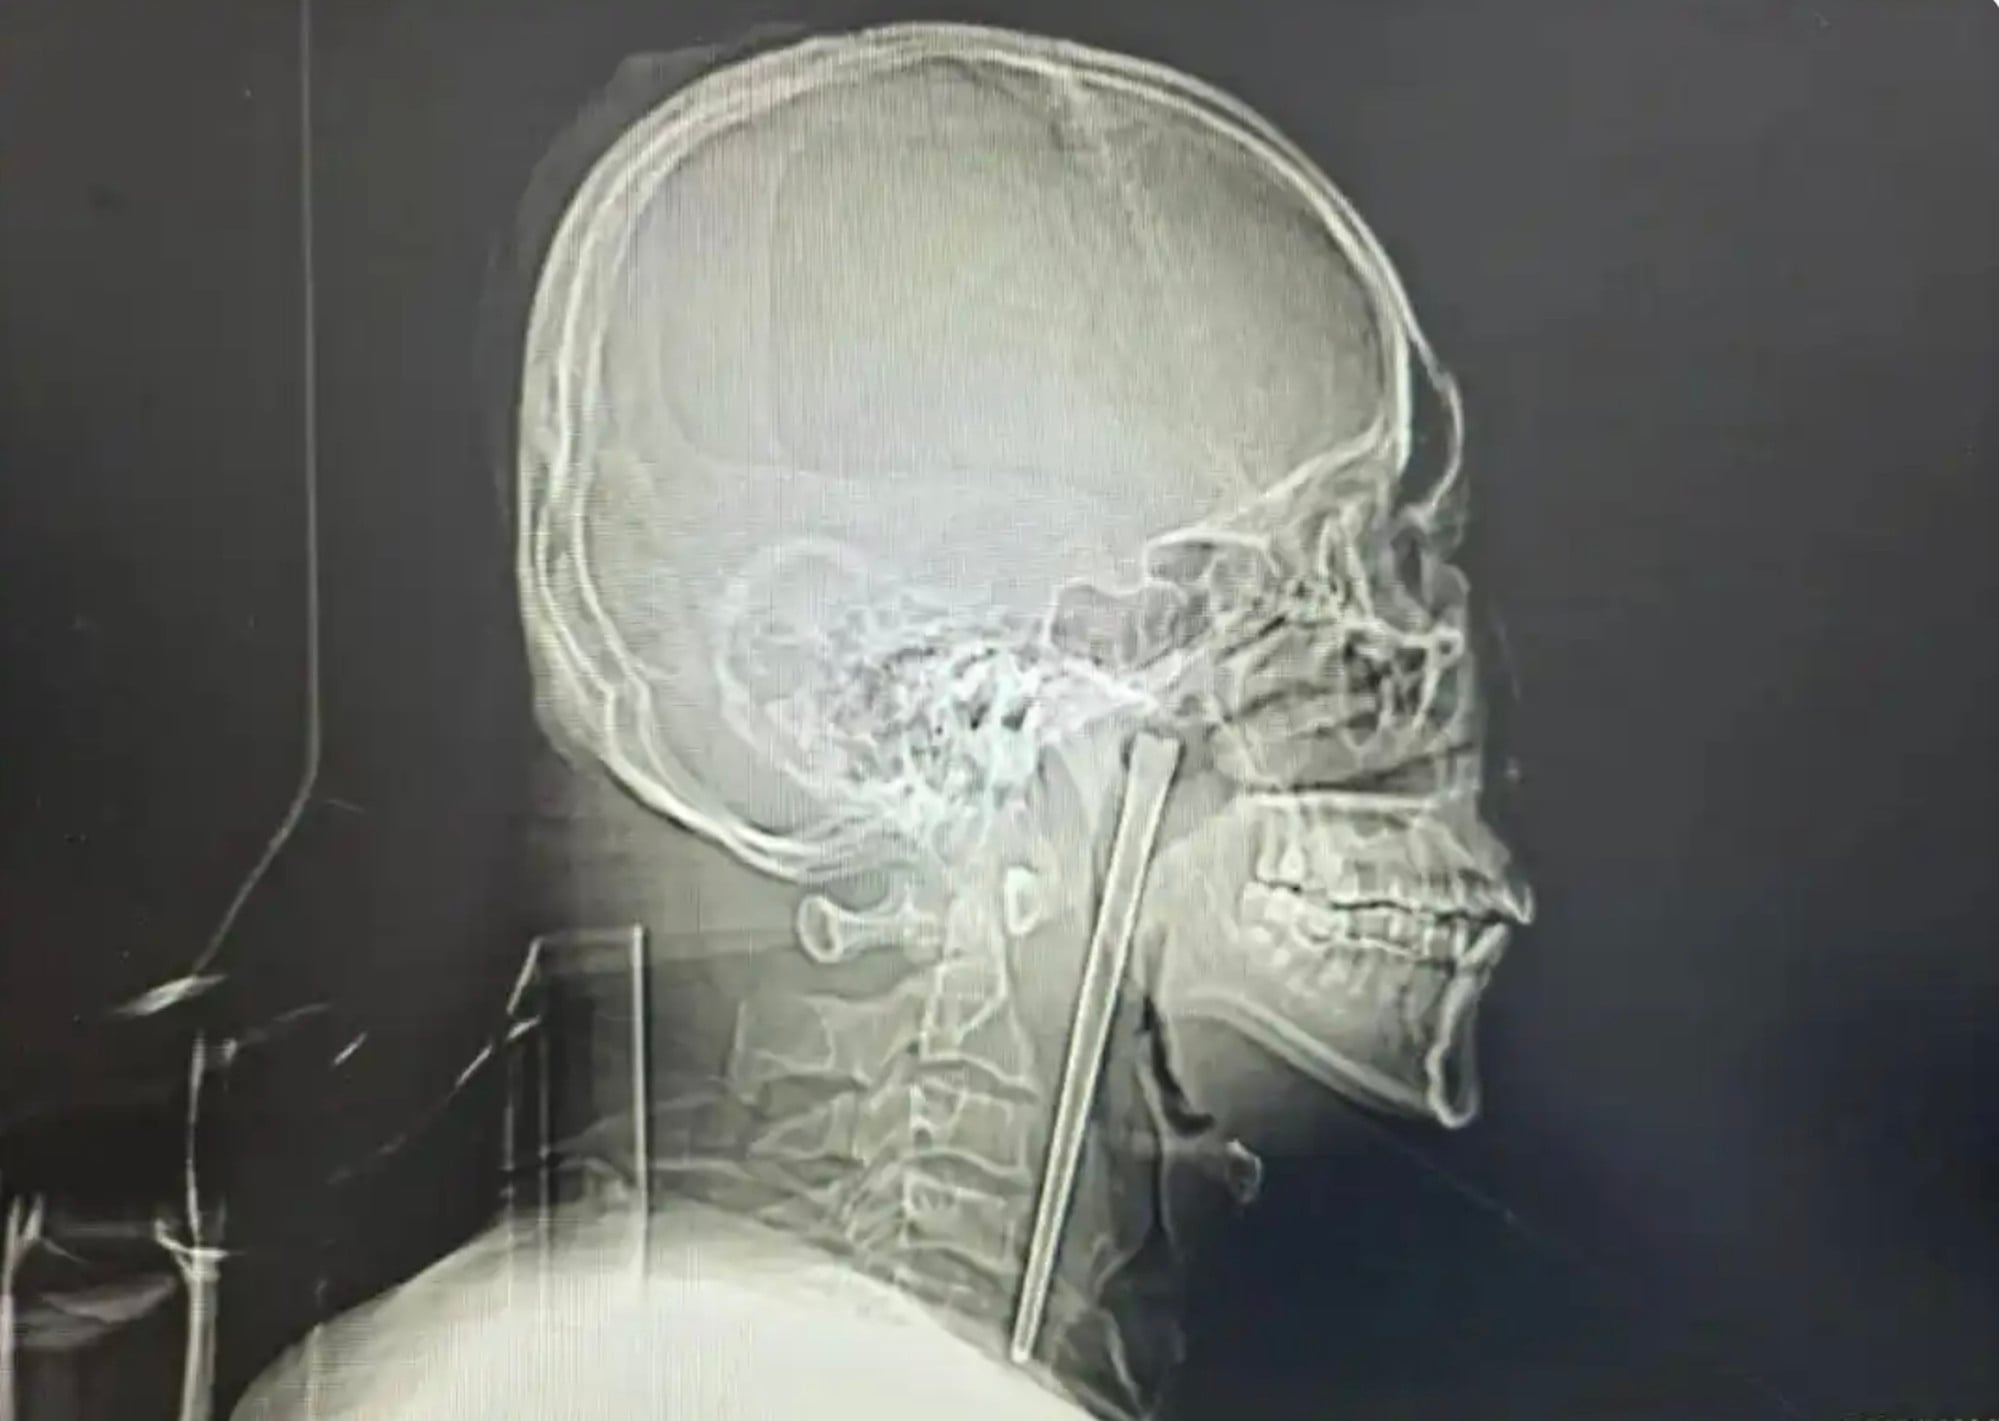

An examination found a metal chopstick in the soft palate of Wang’s throat.

Finally, a 12cm-long metal chopstick was retrieved. The surgery went smoothly, with a small amount of bleeding during the operation.